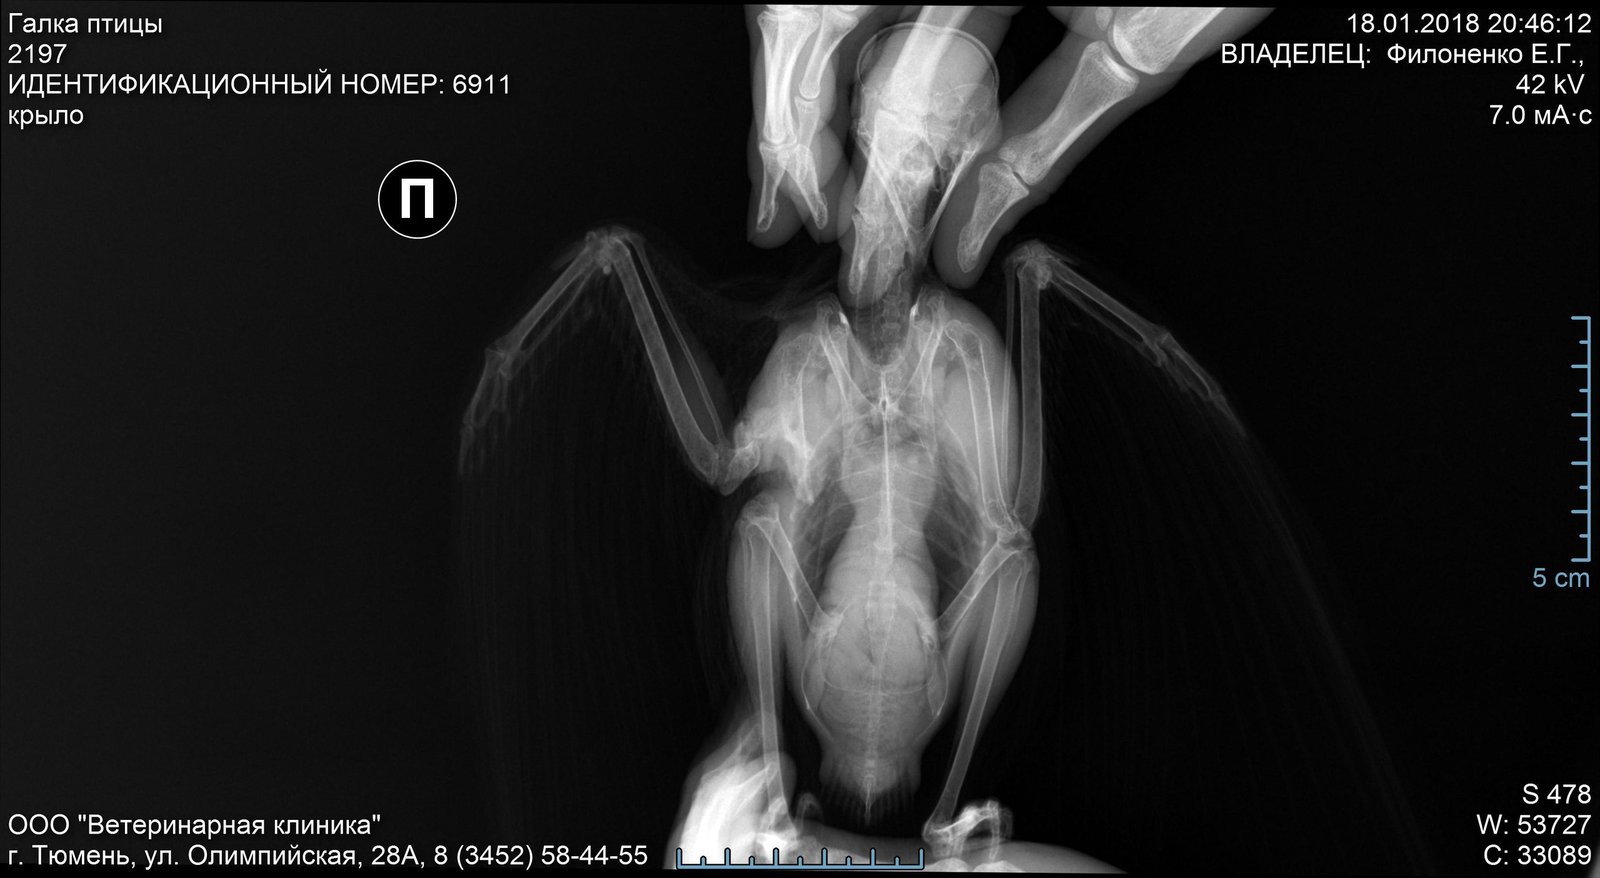

галка с переломом в плечевом суставе

Всем здравствуйте, нам на пмж попала галка, со сломанным крылом. Девушка которая ее нашла сделала и рентген, и сводила к орнитологу.

У нас в Тюмени с хорошими врачами сложно. Они ей даже не наложили повязку. Сама я криворукая, галка вырывается, мне все время кажется что я в обвод крыла делаю что-то неверно и недостаточно натянуто.

Что-то там кажется кость совсем в хлам... покой, зафиксирвоать сетчатым круглым бинтом- под здоровое крыло сделать отверстие- под крыло можно проложить дамскую ежедневку, удобно-мягко,гигроскопично,воздухопроницаемо . Клейкой стороной к корпусу...

И сказали что перелому больше двух месяцев...  Есть ли смысл фиксировать?